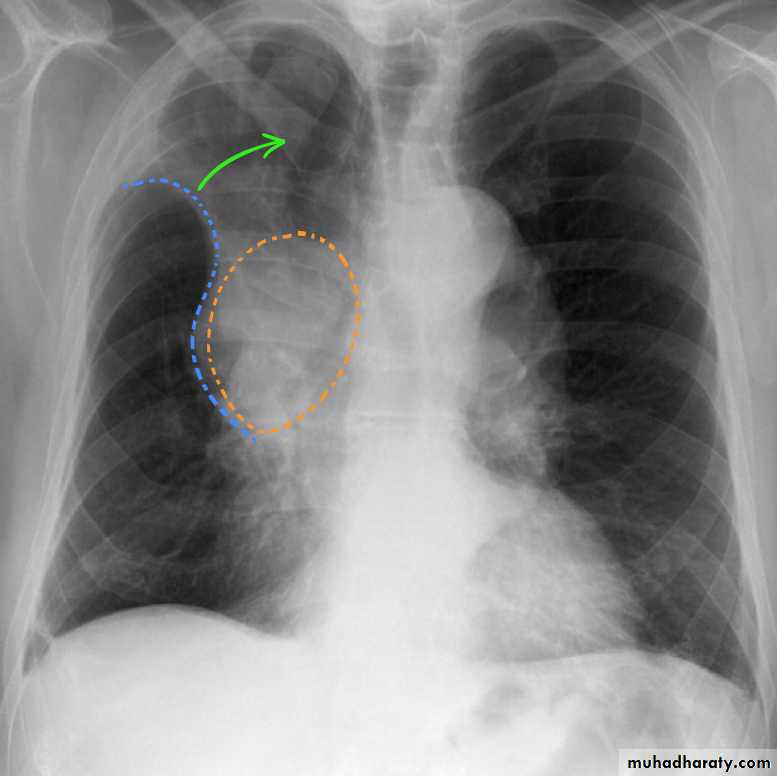

A common cause of lobar collapse is a hilar mass. When a right hilar mass is combined with collapse of the right upper lobe, the result is an S shape to elevated horizontal fissure. This is known as Golden S sign .

Radiology of BGCA

The appearance depends on the location of the lesion.1.The more central lesions may merely appear as a bulky hilum, representing the tumor and local nodal involvement the lesion is irregular in outline have spiky or sun ray spiculation .

2.Lobar collapse may be seen due to obstruction of a bronchus. When the right upper lobe is collapsed and a hilar mass is present, this is known as the Golden S sign.

3.A more peripheral location may appear as a rounded or spiculated mass. Cavitation may be seen as an air-fluid level , more to be large cell CA .

4.Chest wall invasion is difficult to identify on plain films unless there is destruction of the adjacent rib or evidence of soft tissue growing into the soft tissues superficial to the ribs.

5.A pleural effusion may also be seen, and although it is associated with a poor prognosis, not all effusions are due to malignant involvement of the pleural space.